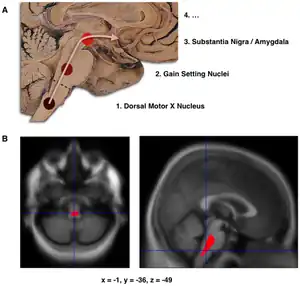

The main pathological characteristics of PD are cell death in the brain's basal ganglia (affecting up to 70% of the dopamine-secreting neurons in the substantia nigra pars compacta by the end of life).[75] In Parkinson's disease, alpha-synuclein becomes misfolded and clump together with other alpha-synuclein. Cells are unable to remove these clumps, and the alpha-synuclein becomes cytotoxic, damaging the cells.[14][89] These clumps can be seen in neurons under a microscope and are called Lewy bodies. Loss of neurons is accompanied by the death of astrocytes (star-shaped glial cells) and an increase in the number of microglia (another type of glial cell) in the substantia nigra.[90] Severity of progression of the parts of the brain affected by PD can be measured with Braak staging. According to this staging, PD starts in the medulla and the olfactory bulb before moving to the substantia nigra pars compacta and the rest of the midbrain/basal forebrain. Movement symptom onset is associated when the disease begins to affect the substantia nigra pars compacta.[19]

- Schematic initial progression of Lewy body deposits in the first stages of PD, as proposed by Braak and colleagues

- Localization of the area of significant brain volume reduction in initial PD compared with a group of participants without the disease in a neuroimaging study, which concluded that brainstem damage may be the first identifiable stage of PD neuropathology[91]